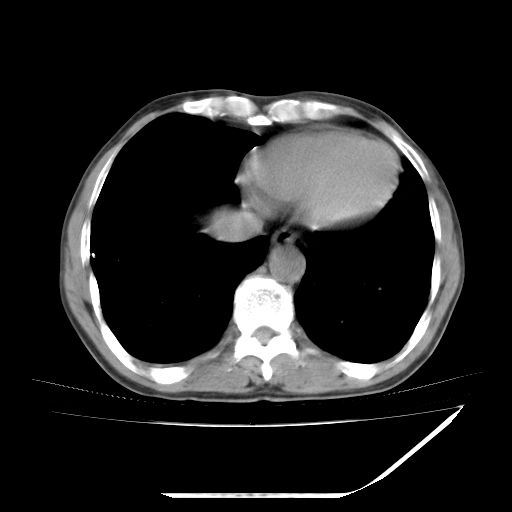

男,59岁,“结核性胸膜炎”30余年,胸部经常疼痛,多次x检查提示“肺部”炎症。腹部疼痛5日,b超提示:“肝内短管结石,余显示不清,建议进一步检查。”

两肺结核并右侧胸腔积液;脾脏、腹腔及腹膜后淋巴结结核[陈旧性];肝内胆管结石

胸部腹部都是结核(双肺。纵隔淋巴结,肝脏,脾脏,肠系膜)

两肺结核并右侧胸腔积液;脾脏、腹腔及腹膜后淋巴结结核[陈旧性];肝内胆管结石。直肠息肉?